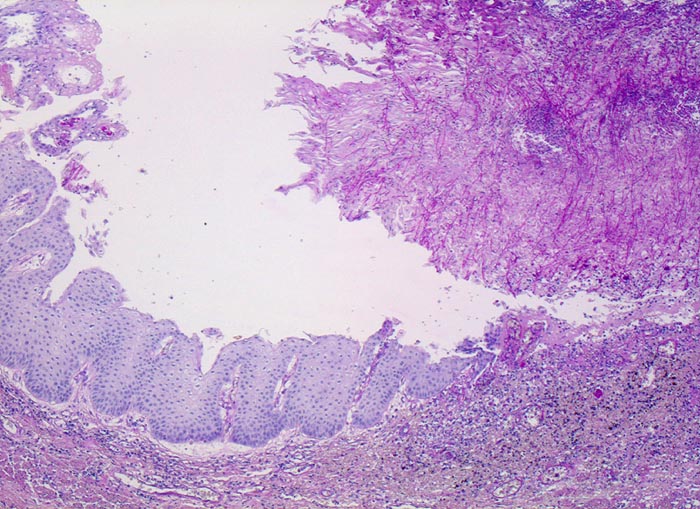

Die Schleimhaut links im Bild ist weitgehend unauffällig. Am rechten Bildrand ist ein Ulkus erkennbar, welches von einem dicken Geflecht aus Pseudohyphen bedeckt wird.

Weisse, streifenförmige Beläge auf der Mucosa

Mann, 75 Jahre, mit bekanntem multiplen Myelom. Autopisepräparat. Progrediente Dysphagie.

Histologie

50